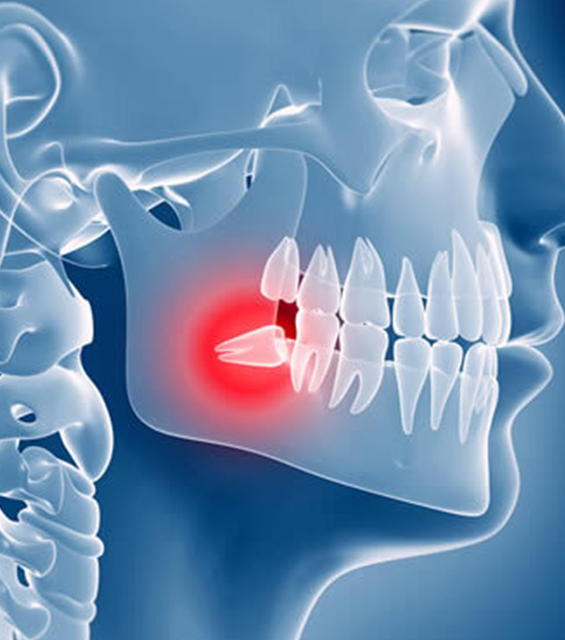

Eights are the teeth that give patients the most problems and inconvenience, especially when erupting in a position that prevents their complete eruption. Quite often, however, the problem is that they hardly fit in the mouth causing a lot of trouble. If the figure eight eruption has stopped and the tooth is invisible, its position is often incorrect, which can damage the roots of the remaining molars. Stopping may be painful and cause swelling. Additionally, eights are most prone to caries because access to them is difficult. This makes it much more difficult to clean them, and the food remaining in their vicinity causes the formation of bacteria.